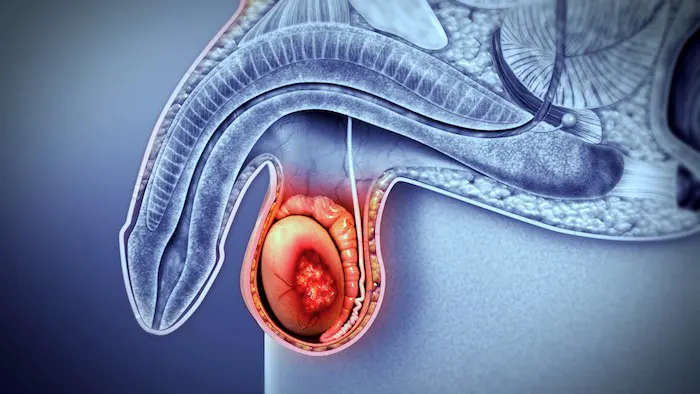

O autoexame testicular deve ser ensinado e praticado por homens jovens, especialmente aqueles com fatores de risco como criptorquidia prévia. Qualquer alteração no tamanho, consistência ou presença de nódulos deve ser imediatamente avaliada por um urologista. Da mesma forma, sintomas como sangue na urina, alterações no jato urinário, dor lombar persistente ou qualquer outro sintoma relacionado ao sistema genitourinário não devem ser ignorados.